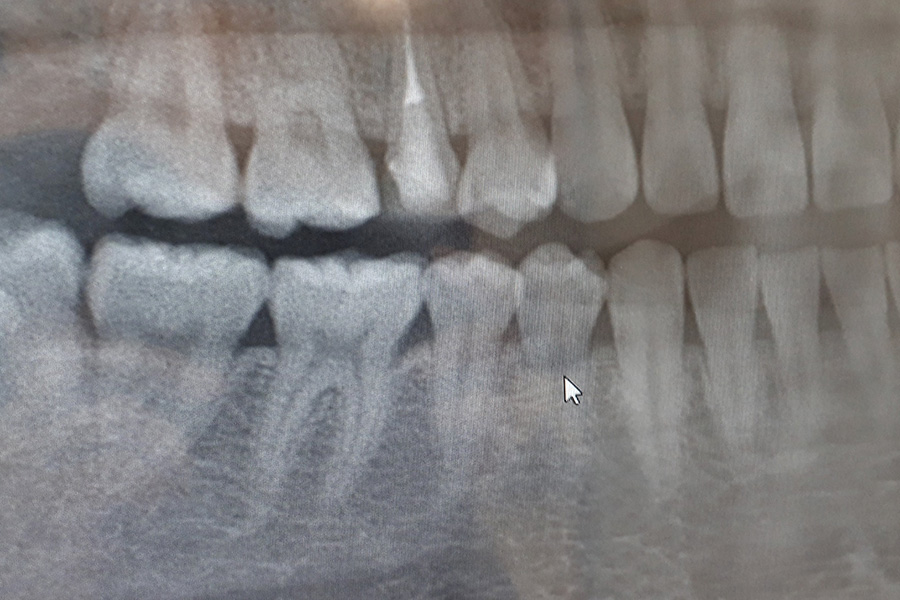

むし歯

むし歯は、初期の段階で発見・治療することで、歯を削る量を最小限に抑え、歯を長く守ることができます。

しかし、むし歯は自然に治ることはなく、放置すると進行してしまいます。

当院では、患者さまのお話を丁寧に伺い、むし歯の進行状況をしっかり確認したうえで、痛みに配慮しながら、できるだけ歯を削らず、抜かない治療を大切にしています。